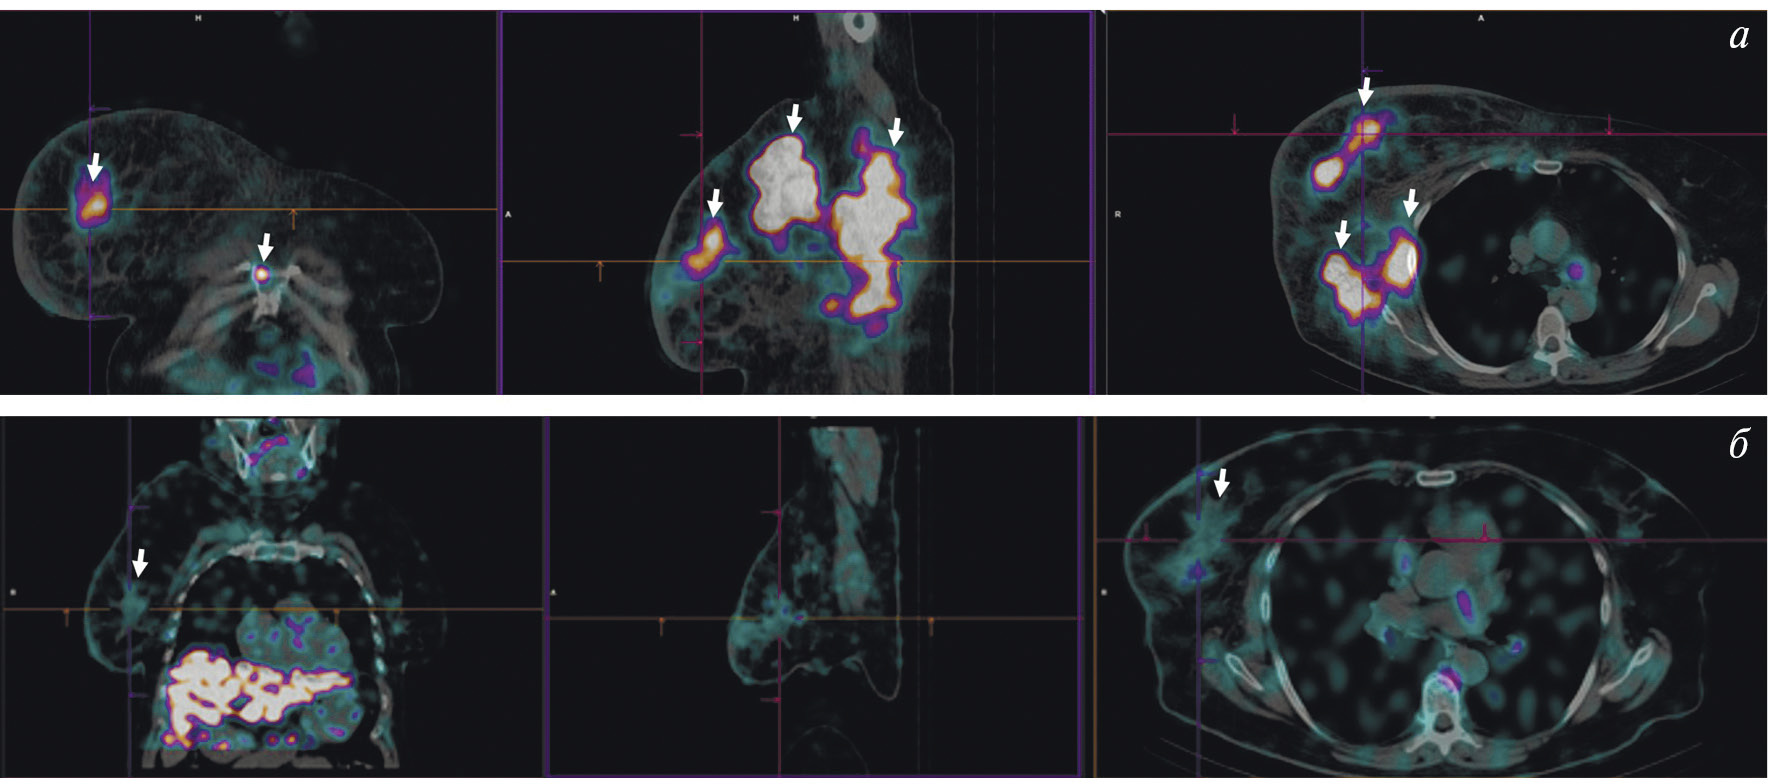

В рутинной клинической практике для ПЭТ/КТ-визуализации опухоли предстательной железы и её метастазов применяются радиофармпрепараты на основе простатспецифических мембранных антигенов, меченных 68Ga ([68Ga]Ga-ПСМА-11, [68Ga]Ga-ПСМА-617, [68Ga]Ga-ПСМА-I&T) либо 18F ([18F]F-DCFPyL, [18F]F-ПСМА-1007) [22, 23]. Главные преимущества меченных 99mТс препаратов, тропных к ПСМА, — невысокая стоимость и доступность технеция-99m, а также возможность визуализации опухоли с помощью гамма-камеры. В настоящее время для этих целей предложен ряд радиофармпрепаратов [24]. В России зарегистрированы наборы для приготовления 99mTc-HYNIC-ПСМА (“ПСМА HYNIC, 99mТс”, Польша; “Проскан, 99mТс”, Россия). Отечественный РФЛП разрабатывался в ТПУ и НИИ онкологии Томского НИМЦ. Клинические испытания 99mТс-ПСМА показали его высокую эффективность при диагностике и стадировании рака простаты, а также при отборе на радиолигандную терапию и оценке её воздействия (рис. 4).

Рис. 4. ОФЭКТ с 99mТс-ПСМА пациента с раком простаты до (а) и после (б) четырёх курсов радиолигандной терапии 177Lu-ПСМА

Показания к радионуклидной диагностике с указанными выше препаратами — стадирование рака предстательной железы до начала лечения (хирургического вмешательства или лучевой терапии) [25] и диагностика рецидива опухоли после радикального лечения [25]. Кроме того, радиофармпрепараты на основе ПСМА участвуют в отборе пациентов с метастатическим кастрационно-резистентным раком предстательной железы на ПСМА-направленную радиолигандную терапию. Такая визуализация необходима для определения наличия и интенсивности гиперэкспрессии простатспецифического мембранного антигена в потенциальных мишенях для радионуклидной терапии [26].

Опубликовано множество работ, сообщающих о высокой эффективности радионуклидной терапии с 177Lu-ПСМА-617 (Pluvicto, Novartis) у пациентов с метастатическим кастрационно-резистентным раком предстательной железы. В частности, в многоцентровом исследовании “Vision” показано, что препарат 177Lu-ПСМА-617, по сравнению с традиционным лечением, позволяет повысить выживаемость без прогрессирования (с 3.4 до 8.7 месяцев) и общую выживаемость (с 11.3 до 15.3 месяцев) пациентов с данным заболеванием [27]. Для лечения метастатического рака предстательной железы также перспективен 225Ac-ПСМА. Он продемонстрировал эффективность при лечении больных, получивших заметные миелотоксические осложнения после предыдущих курсов с 177Lu-ПСМА либо вовсе не показавших положительной динамики [28].